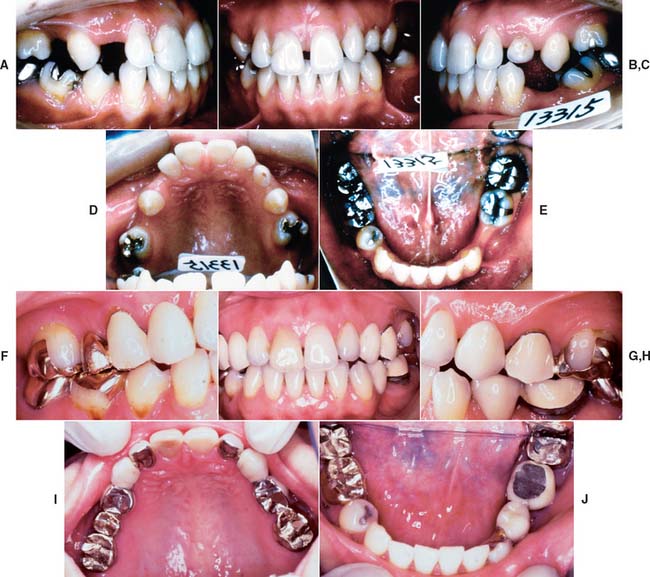

Patients with cast restorations should attend recall visits at least every 6 months. Less frequent recall may lead to oversight of recurrent caries or the development of periodontal disease. Patients who have been provided with extensive fixed prostheses (Fig. 32-6) need more frequent recall appointments, particularly when advanced periodontal disease was present. The appointments can be coordinated by the restorative dentist or the periodontist. To ensure treatment continuity, it is imperative to establish in advance who will assume primary responsibility for coordinating recall appointments.

Fig. 32-6 Patients who have received extensive treatment of this nature require more frequent follow-up care.